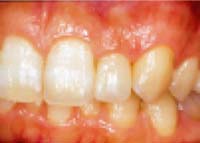

■ダイレクトベニア■

施術前

施術後

前歯の2番目の歯をご覧下さい。

施術前と施術後では、見た目はもとより咬み合わせも良くなっているのがおわかり頂けます。